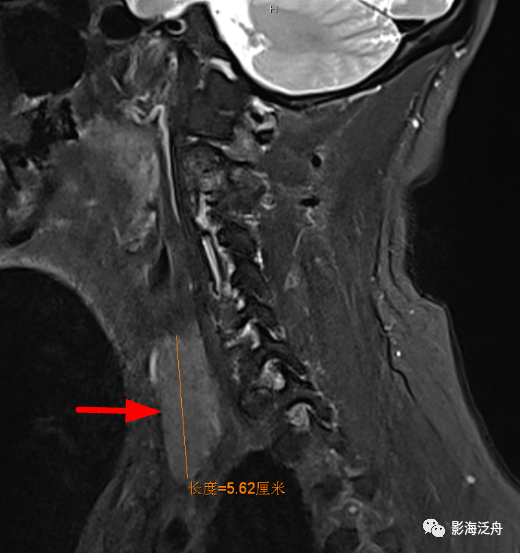

矢状位上另一个需要观察的就是齿状突的高度,异常增高往往是颅底凹陷症导致的(红线为钱氏线)。